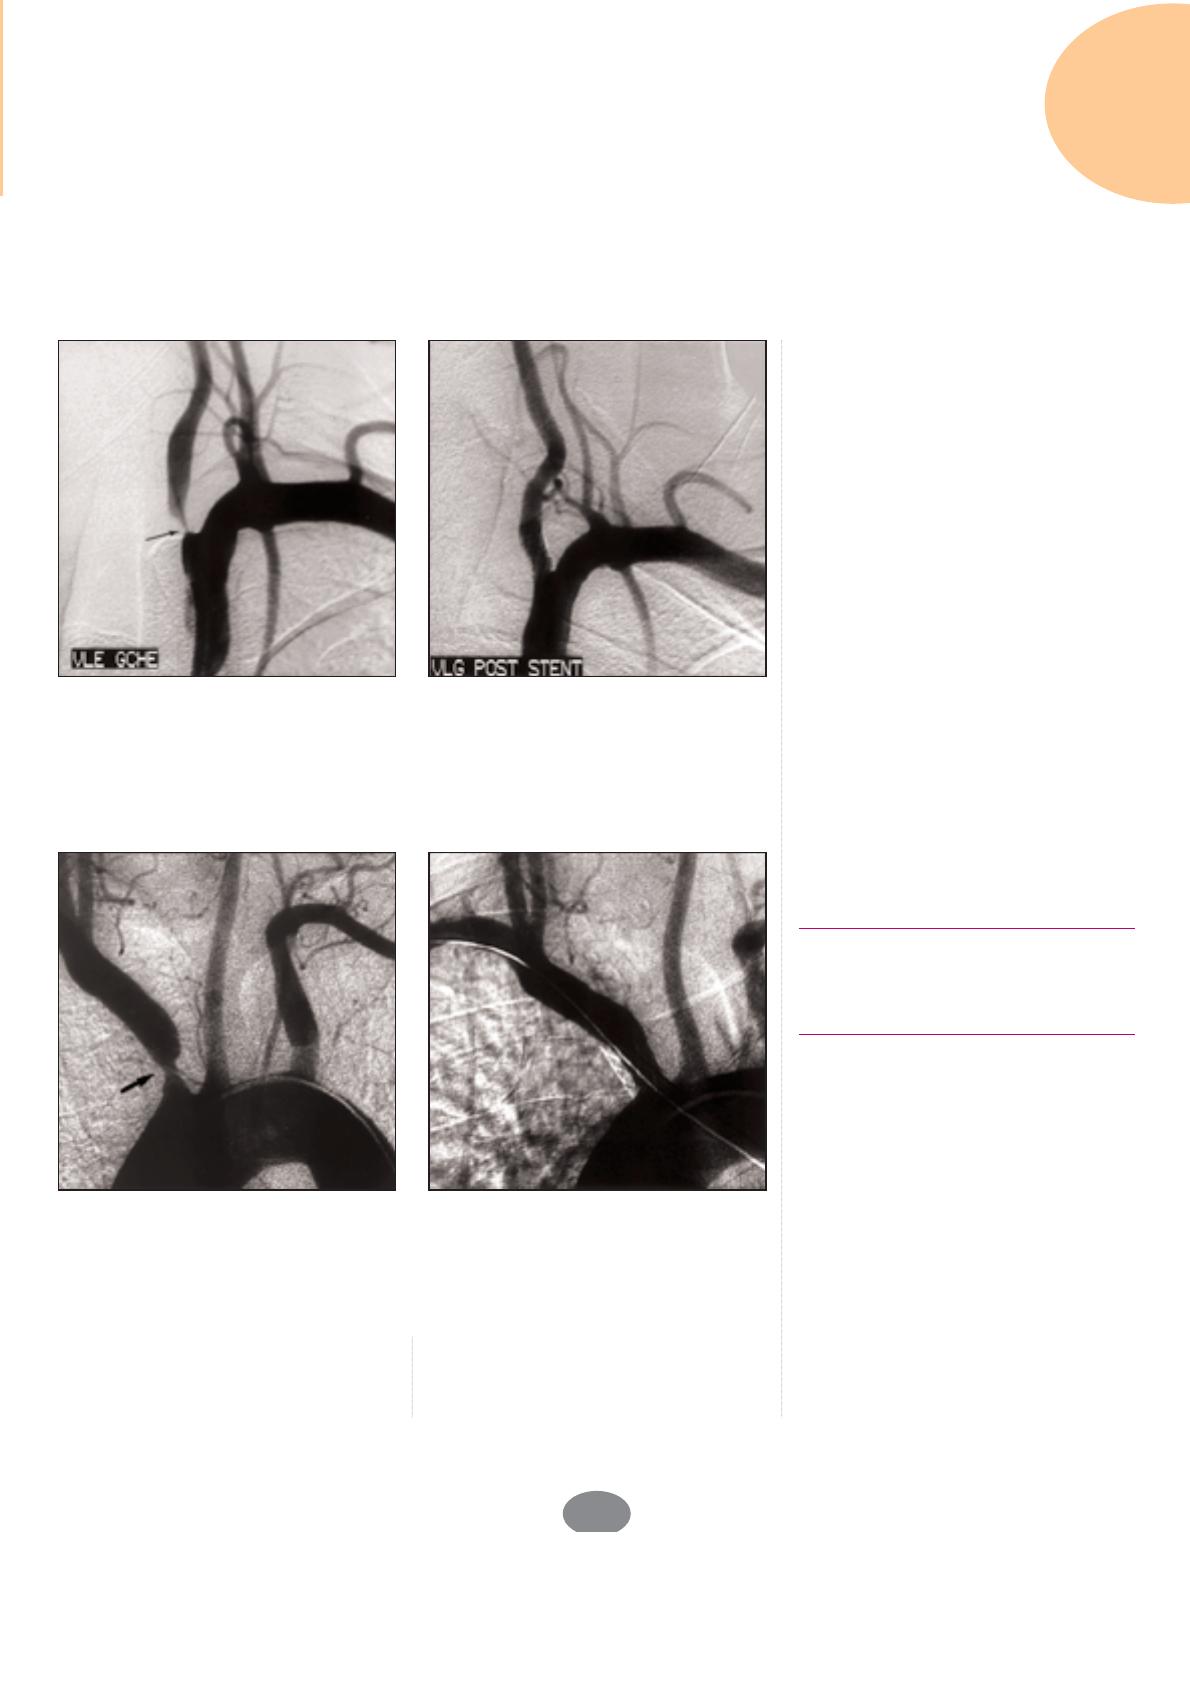

Figure 4. Angioplastie d’une sténose de la bifurcation carotidienne. Patient de 60 ans

aux antécédents de radiothérapie cervicale pour néoplasie ORL ayant présenté plusieurs

épisodes d’hémiparésie droite. Le doppler cervical a montré une thrombose de l’artère

carotide droite et une sténose serrée de l’artère carotide interne gauche.

A : Artériographie carotidienne gauche montrant une sténose très serrée de l’artère caro-

tide interne (pointe de flèche) associée à une image d’excavation (flèche creuse) et à une

plaque sténosante de la bifucation carotidienne (flèche).

B : Résultat après angioplastie et implantation d’un stent autoexpansible